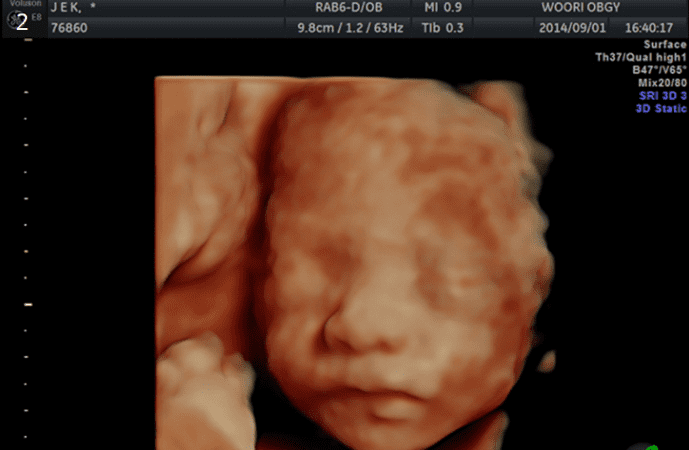

4D 입체영상초음파

입체영상초음파는 선택검사이며, 예약이 필요합니다. 태아의 얼굴, 손, 발, 척추 등이 가장 잘 보이는 임신 23-28주 사이에 실시하여 실물과 유사한 사진을 얻어 미리 아가를 만나볼 수 있는 검사입니다. 우리산부인과는 보다 감각 있는 사진을 위하여 초음파 "GE HD live "을 사용하고 있습니다.